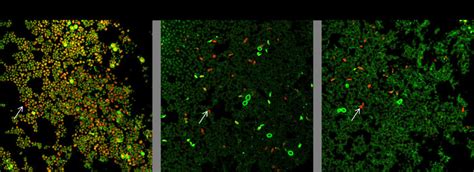

- Antibiofilm Activity Of Bioinspired Peptides And Cytotoxicity. (a ...

- Antibiofilm Activity Of Agnps Against C. Auris Preformed Biofilms. The ...